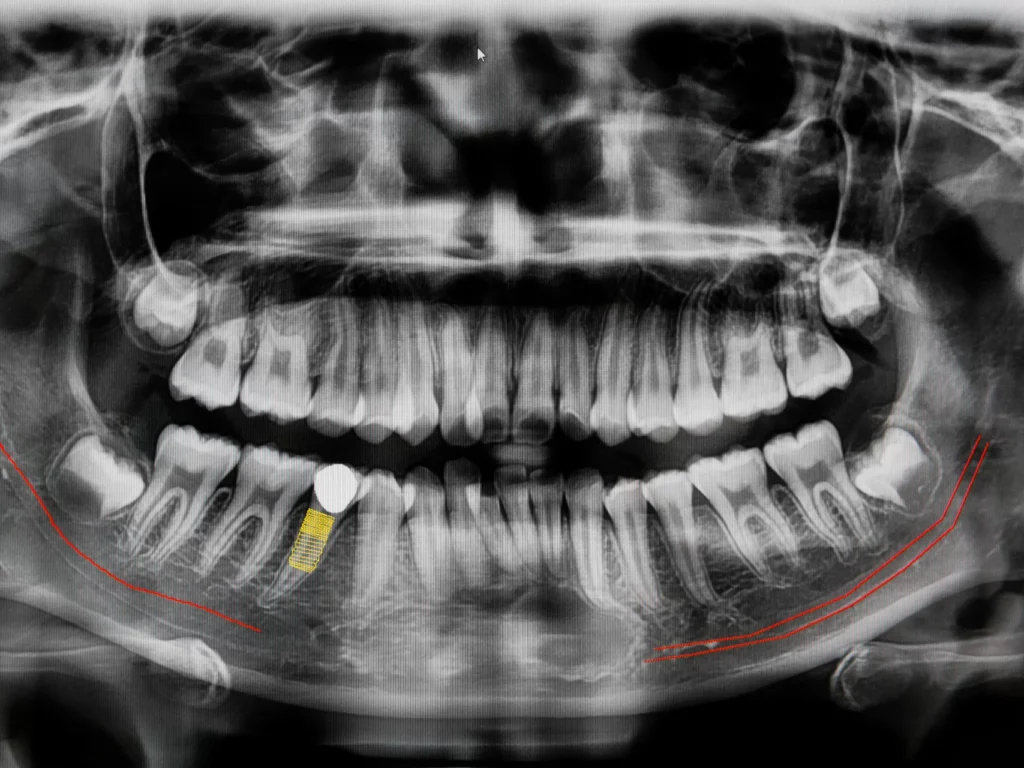

3D Imaging (CBCT)

CBCT stands for ConeBeam Computed Tomography, which is a special type of digital x-ray scanner that dentists use to see a 3D image of your mouth and teeth.

The ConeBeam CT imaging system rotates once around your head while you stand or sit in a chair. The process is quick, simple, and completely painless. We use these scans to provide the best treatment in dental implants, root canals, diagnosis of dental and facial pain, etc.

We can evaluate your teeth and facial structures from literally every angle, in 3D, and in color! Routine x-rays, on the other hand, produce a single flat image with limited information.

You can have absolute confidence and satisfaction in the treatment you receive, knowing we’ve analyzed every problem with 3D technology.